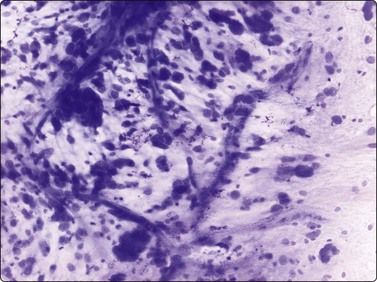

Fibromatoses such as desmoid fibromatosis and palmar and plantar fibromatosis may partly resemble the pseudosarcomatous lesions, especially nodular fasciitis, in FNB smears. However, the nuclei are more consistently spindle and the marked nuclear pleomorphism in those lesions is not seen. Collagen fragments are common and myxoid ground substance unusual, as are inflammatory cells. Strands and clusters of spindle cells showing moderate anisokaryosis, and more or less acellular fragments of collagen are characteristic of desmoid fibromatosis, abdominal as well as extra-abdominal, in FNB smears (Fig. 15.6). When the tumor infiltrates striated muscle, muscle fragments and regenerating multinucleated muscle fibers are commonly seen (Fig. 15.7). The most important differential diagnoses are the rare low-grade malignant fibrosarcoma and monophasic fibrous synovial sarcoma. Smears from palmar and plantar fibromatoses (Dupuytren) can be surprisingly cellular, but the cells are uniformly spindled with bland spindled nuclei (Fig. 15.8). Recent summaries of the cytologic characteristic features of desmoid fibromatosis have been published 20038 and 2006.18

image

Fig. 15.6 Desmoid fibromatosis

The two typical components are shown here: a cluster of loosely cohesive ovoid or spindle fibroblasts and a fragment of collagenous stroma (MGG, HP).

Fig. 15.7 Desmoid fibromatosis

Muscle fragments and regenerating multinucleated muscle fibers are commonly seen (H&E, HP).